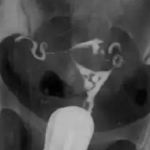

宫腔粘连全景彩超检查 2020/04/10 分类:宫腔粘连 1566 0全景彩超检查是诊断宫腔粘连的有效方法,能明确粘连的部位及程度、宫腔内膜的厚度,是一种无创检查。 标签:宫腔粘连检查 上一篇: 宫腔粘连检查动态数字化子宫输卵管造影 下一篇: 宫腔粘连检查之宫腔镜